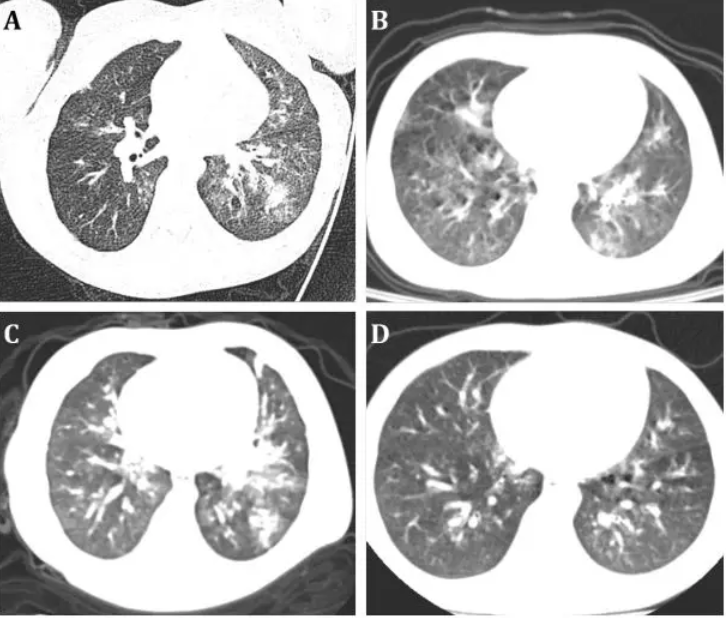

经影像学评估,6名患儿中有4名患有肺炎,胸部CT扫描显示典型的病毒性肺炎类型。

123